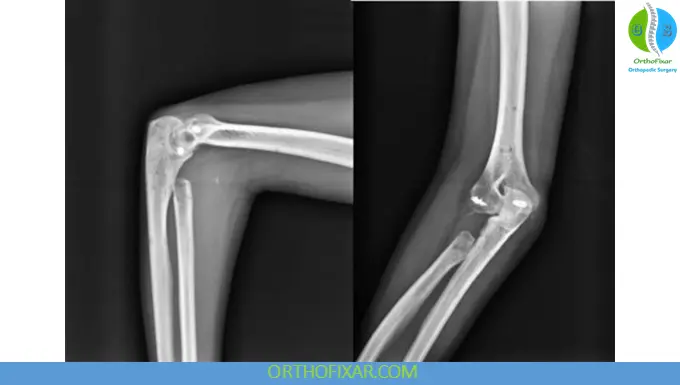

- Type IV: Radial head fracture with elbow dislocation

Essex-Lopresti Lesion

A complex injury involving:

- Radial head fracture

- Interosseous membrane disruption

- DRUJ instability

Key point:

- Do NOT excise the radial head

→ leads to proximal radial migration

Management:

- Radial head repair or replacement

- Stabilization of DRUJ